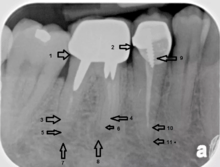

Another common complication of root canal therapy is when the entire length of the root canal is not completely cleaned out and filled (obturated) with root canal filling material (usually gutta percha). The X-ray in the right margin below shows two adjacent teeth that had received bad root canal therapy. The root canal filling material (3, 4 & 10) does not extend to the end of the tooth roots (5, 6 & 11). The dark circles at the bottom of the tooth roots (7 & 8) indicated infection in the surrounding bone. Recommended treatment is either to redo the root canal therapy if possible or extract the tooth and place dental implant(s). [31]